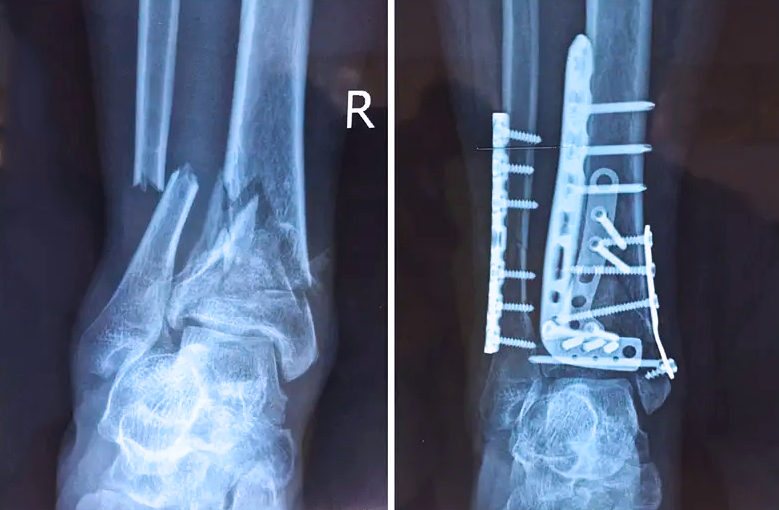

踝關(guān)節(jié)是人體中負(fù)重較大的關(guān)節(jié),也是活動(dòng)度較大的地方,所以對(duì)于足踝部位的關(guān)節(jié)內(nèi)骨折,我們更需要做到“解剖復(fù)位”。對(duì)于這種關(guān)節(jié)內(nèi)的骨折,尤其是踝關(guān)節(jié)內(nèi)部的骨折,不僅需要進(jìn)行X影像平片正側(cè)位的拍攝,由于在二維影像上無(wú)法判斷關(guān)節(jié)面的受損情況,往往還需要進(jìn)行三維影像的檢查。

在術(shù)前,我們需要做三維掃描的CT檢查,我們必須要有CT的片子,還要有三維的重建。

在術(shù)中,我們?cè)趺慈ヅ袛嚓P(guān)節(jié)面平不平整呢?常規(guī)的正側(cè)位影像是不能判斷的。有些醫(yī)生為了準(zhǔn)確的判斷,可能會(huì)選擇做開(kāi)放性的手術(shù),把關(guān)節(jié)暴露出來(lái),在眼睛的直視下判斷關(guān)節(jié)面平不平整。但是關(guān)節(jié)全部打開(kāi),無(wú)疑增加了病人的創(chuàng)傷,而且增加了患者的恢復(fù)時(shí)間。所以如果在術(shù)中我們有三維影像的支持,對(duì)醫(yī)生做手術(shù)而言就會(huì)事半功倍,而且能夠大大的增加手術(shù)準(zhǔn)確度,增加患者術(shù)后的預(yù)后。所以在術(shù)中有三維影像的支持是非常必要的!